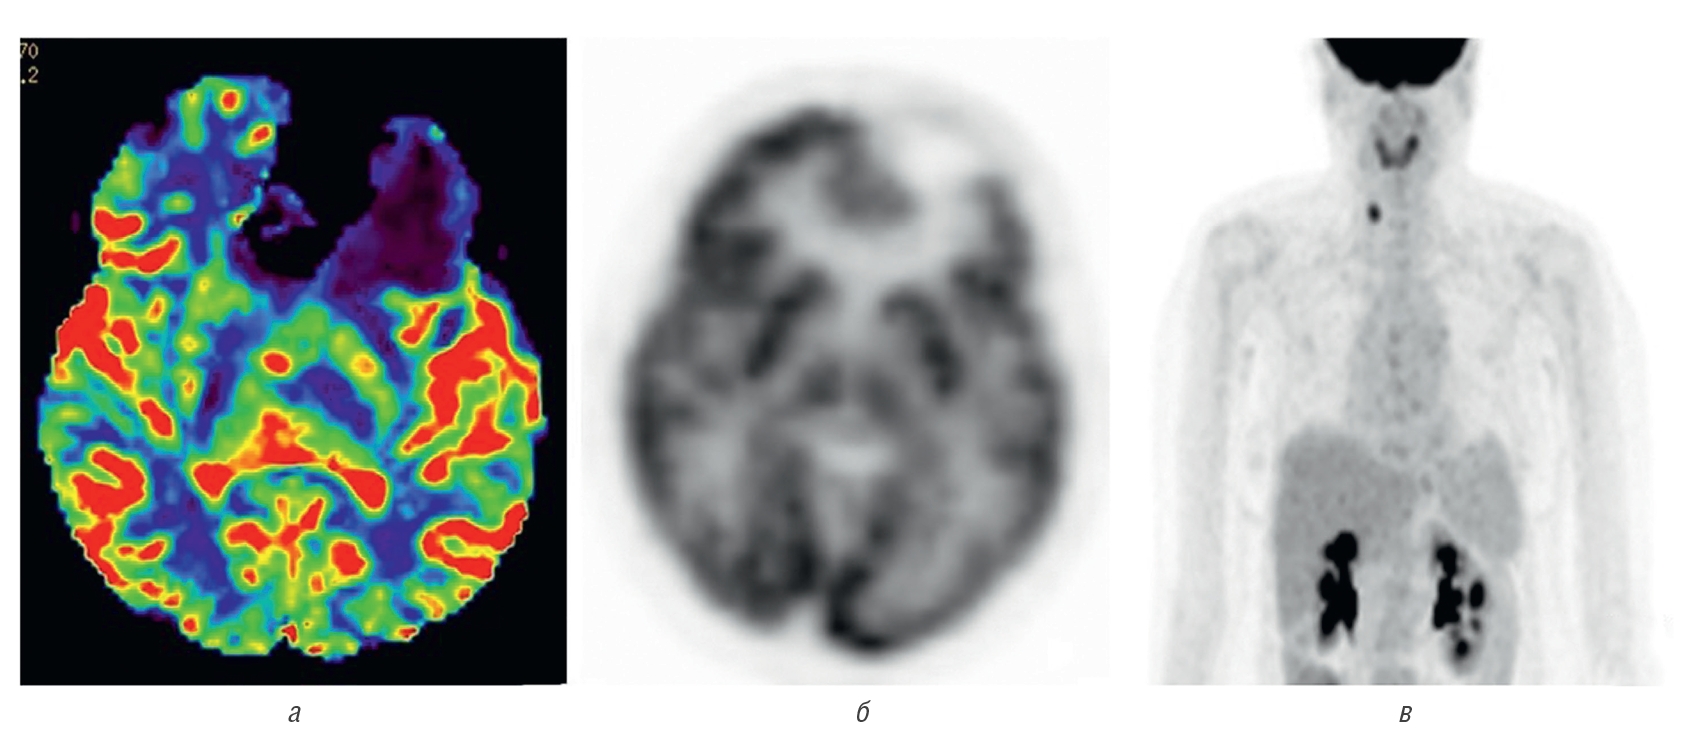

Заключение ПЭТ-КТ 03.10.2022 | Гипоплотная аметаболичная зона лобной доли слева (состояние после хирургического лечения); образования с гиперфиксацией РФП правой доли щитовидной железы неясного генеза; гепатомегалия, жировая инфильтрация печени; жидкостное образование селезенки (рис. 9) |

Рис. 9. a — карта МР-перфузии CBV: отмечается обширная зона гипоперфузии в зоне удаленной опухоли и снижение показателей в зоне отека; б — ПЭТ изображение в аксиальной проекции с 18F-ФДГ: данные коррелируют с МР-перфузией; в — на ПЭТ изображении всего тела 18F-ФДГ выявляется очаг повышенной аккумуляции радиофармацевтического препарата в проекции правой доли щитовидной железы

Fig. 9. a — map of CBV MR perfusion shows an extensive hypoperfusion zone in the area of the removed tumor and a decrease in indicators in the area of edema; б — PET image in axial projection with 18F-FDG data correlate with MR perfusion; в — PET image of the entire body of 18F-FDG reveals a focus of increased accumulation of radiopharmaceutical drug in the projection of the right lobe of the thyroid gland